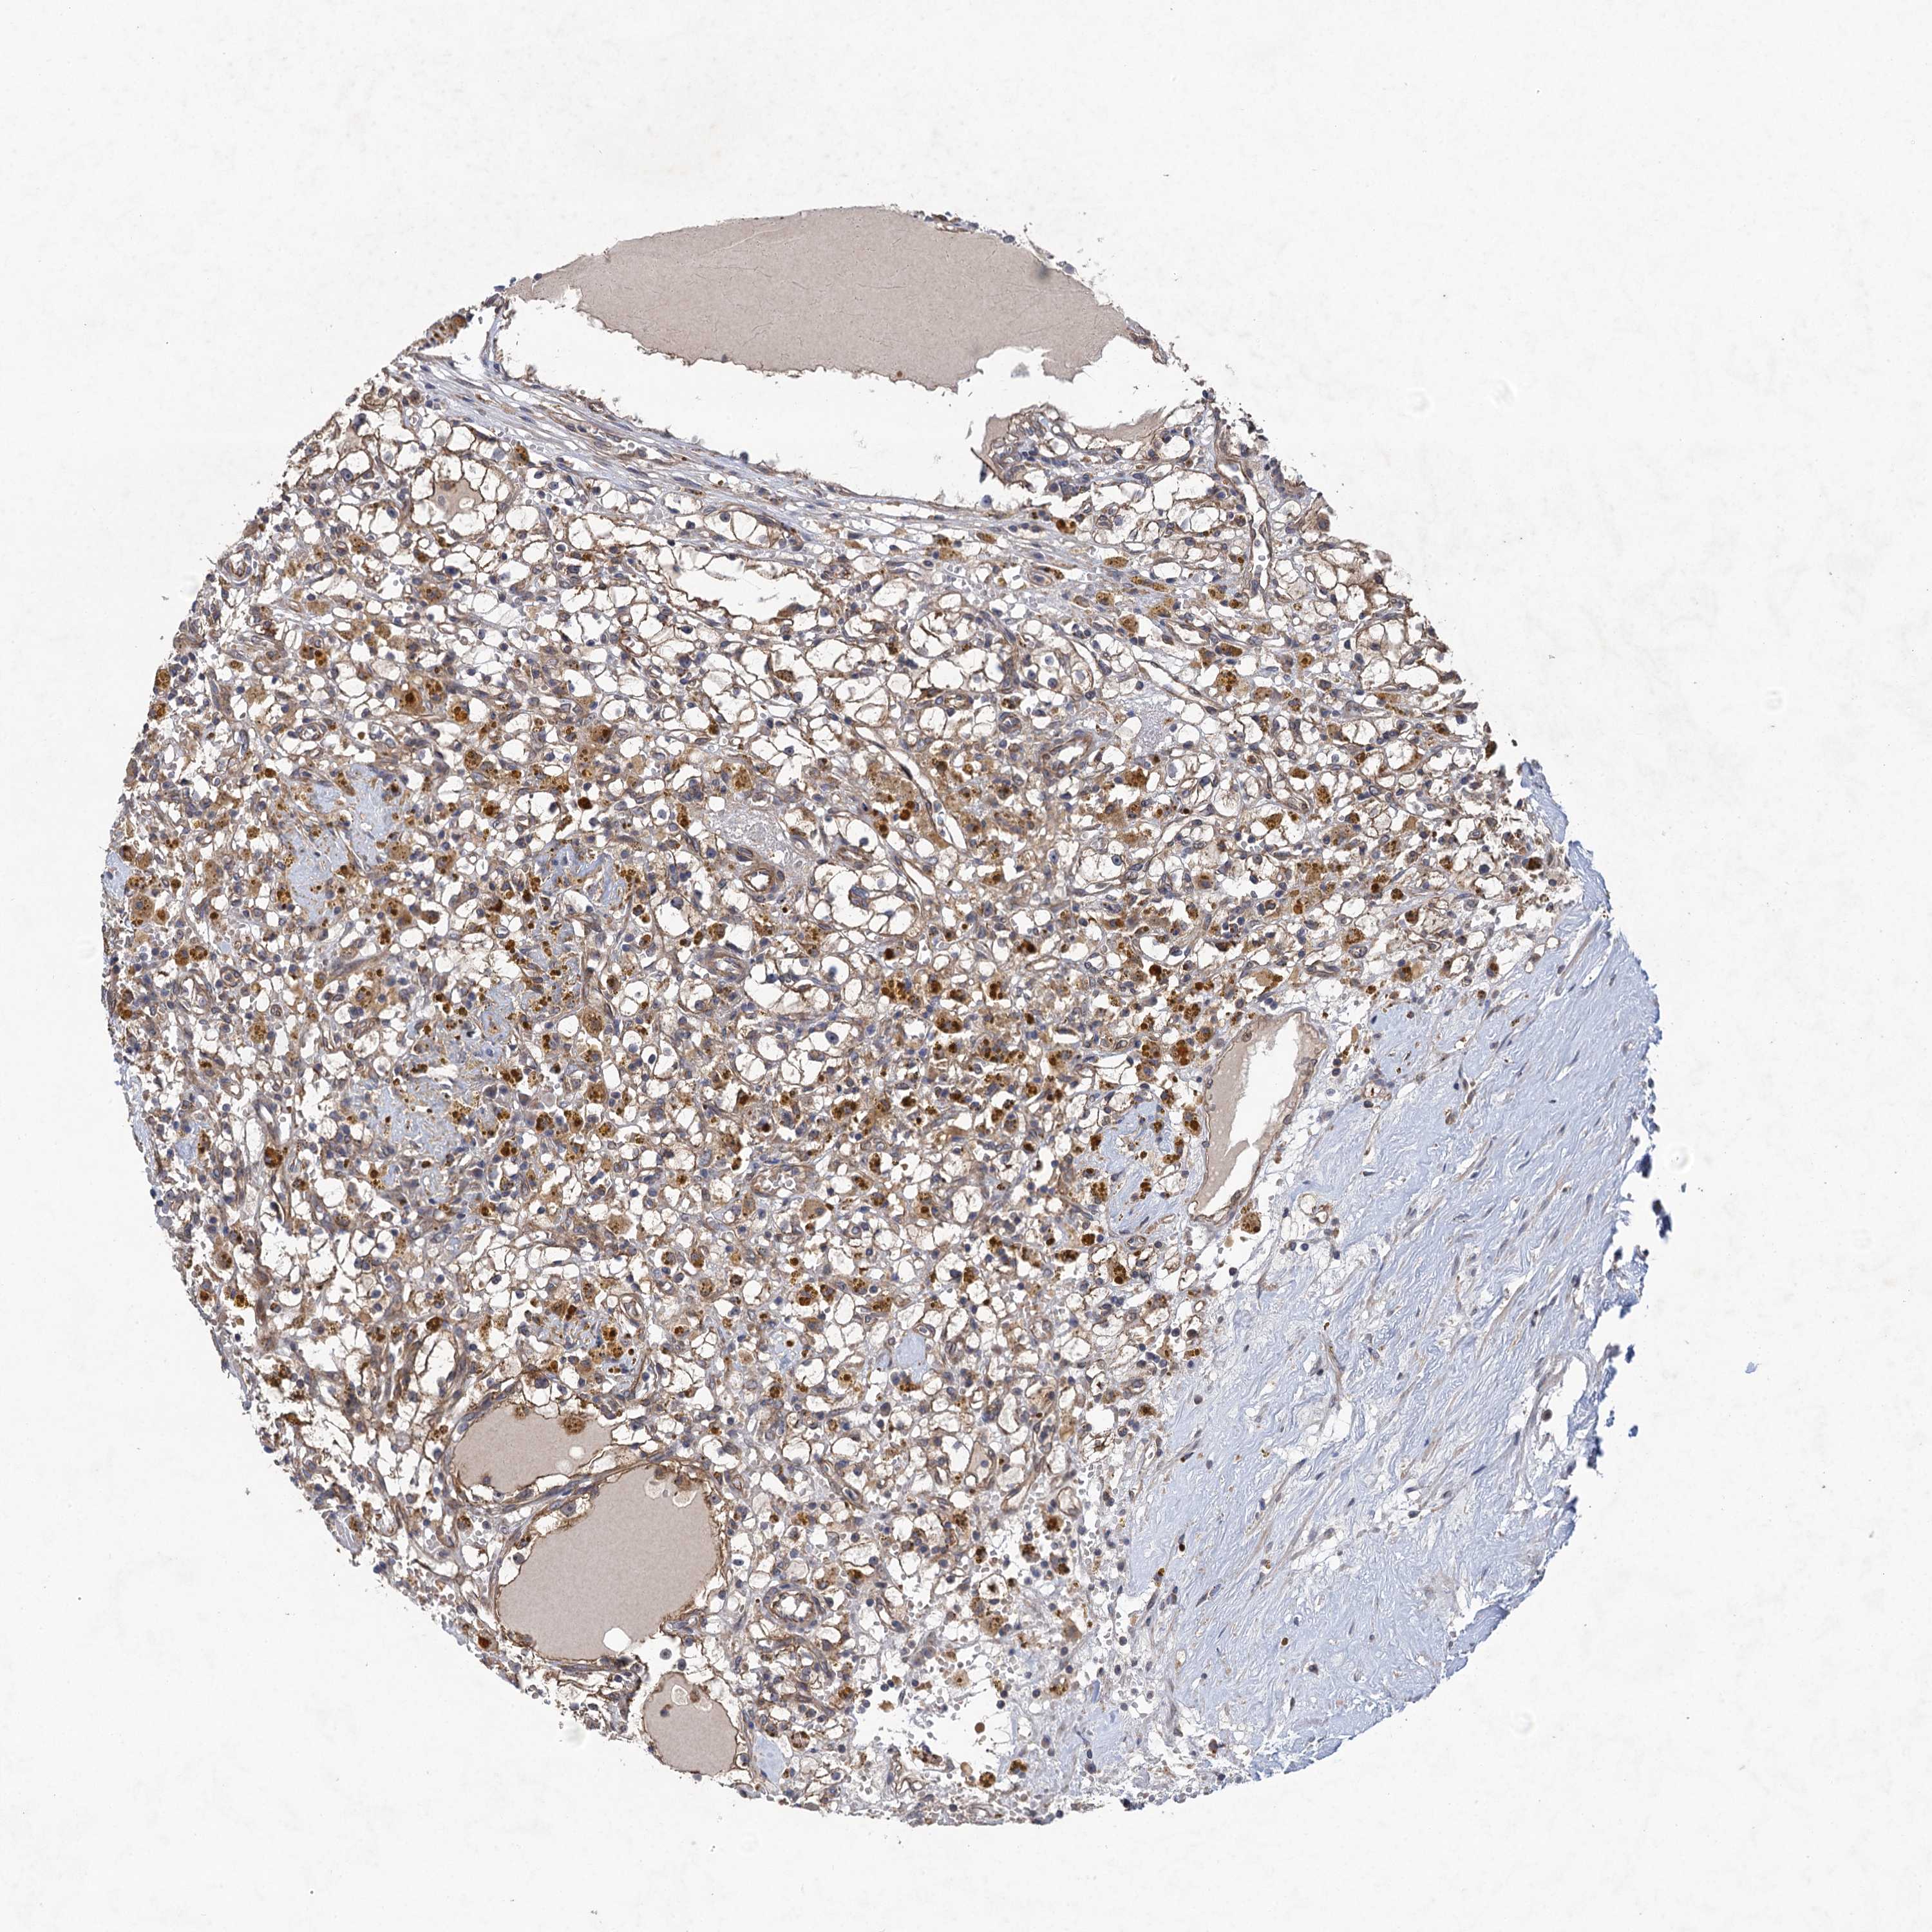

KIDNEY RENAL CLEAR CELL CARCINOMA (VALIDATION) - Interactive survival scatter ploti

The Survival Scatter plot shows the clinical status (i.e. dead or alive) for all individuals in the patient cohort, based on the same data that underlies the corresponding Kaplan-Meier plots. Patients that are alive at last time for follow-up are shown in blue and patients who have died during the study are shown in red.

The x-axis shows the expression levels (FPKM) of the investigated gene in the tumor tissue at the time of diagnosis. The y-axis shows the follow-up time after diagnosis (years). Both axes are complimented with kernel density curves demonstrating the data density over the axes. The top density plot shows the expression levels (FPKM) distribution among dead (red) and alive patients (blue). The right density plot shows the data density of the survived years of dead patients with high and low expression levels respectively, stratified using the cutoff indicated by the vertical dashed line through the Survival Scatter plot. This cutoff is automatically defined based on the FPKM cutoff that minimizes the p-score. The cutoff can be changed by dragging the vertical line or by entering a cutoff value in the square labeled "Current cut-off".

Under the Survival Scatter plot the p-score landscape (black curve; left axis) is shown together with dead median separation (red curve; right axis). Dead median separation is the difference in median mRNA expression between patients who have died with high and low expression, respectively. It is calculated as follows: median FPKM expression of dead patients with high expression - median FPKM expression of dead patients with low expression. This is intended to aid the user in visually exploring custom cutoffs and the associated p-scores and dead median separation.

Individual patient data is displayed and can be filtered by clicking on one or more of the category buttons on the top of the page. Categories describing expression level and patient information include: high, low, alive, dead, female, male and tumor stages. The scale of the x-axis can be toggled between linear and log-scale by clicking on the "x log" button. Mouse-over function shows TCGA ID, patient information and mRNA expression (FPKM) for each patient.

& Survival analysisi

Kaplan-Meier plots summarize results from analysis of correlation between mRNA expression level and patient survival. Patients were divided based on level of expression into one of the two groups "low" (under cut off) or "high" (over cut off). X-axis shows time for survival (years) and y-axis shows the probability of survival, where 1.0 corresponds to 100 percent.

HAUS1 is not prognostic in Kidney Renal Clear Cell Carcinoma (validation)

Best expression cut offi

Based on the FPKM value of each gene, patients were classified into two groups and association between prognosis (survival) and gene expression (FPKM) was examined. The best expression cut-off refers the FPKM value that yields maximal difference with regard to survival between the two groups at the lowest log-rank P-value. Best expression cut-off was selected based on survival analysis .

When clicking on this number, the vertical dashed line indicating cut-off, the interactive survival plot, and the Kaplan-Meier curve will be adjusted to show results based on the best expression cut-off.

: 22.86

P scorei

Log-rank P value for Kaplan-Meier plot showing results from analysis of correlation between mRNA expression level and patient survival.

N/A

TCGA RNA samplesi

RNA-seq data is reported as average FPKM (number Fragments Per Kilobase of exon per Million reads), generated by the The Cancer Genome Atlas (TCGA) .

Normal distribution across the dataset is visualized with box plots, shown as median and 25th and 75th percentiles. Points are displayed as outliers if they are above or below 1.5 times the interquartile range. FPKM values of the individual samples are presented next to the box plot.

Average pTPM 19.7

Number of samples 100